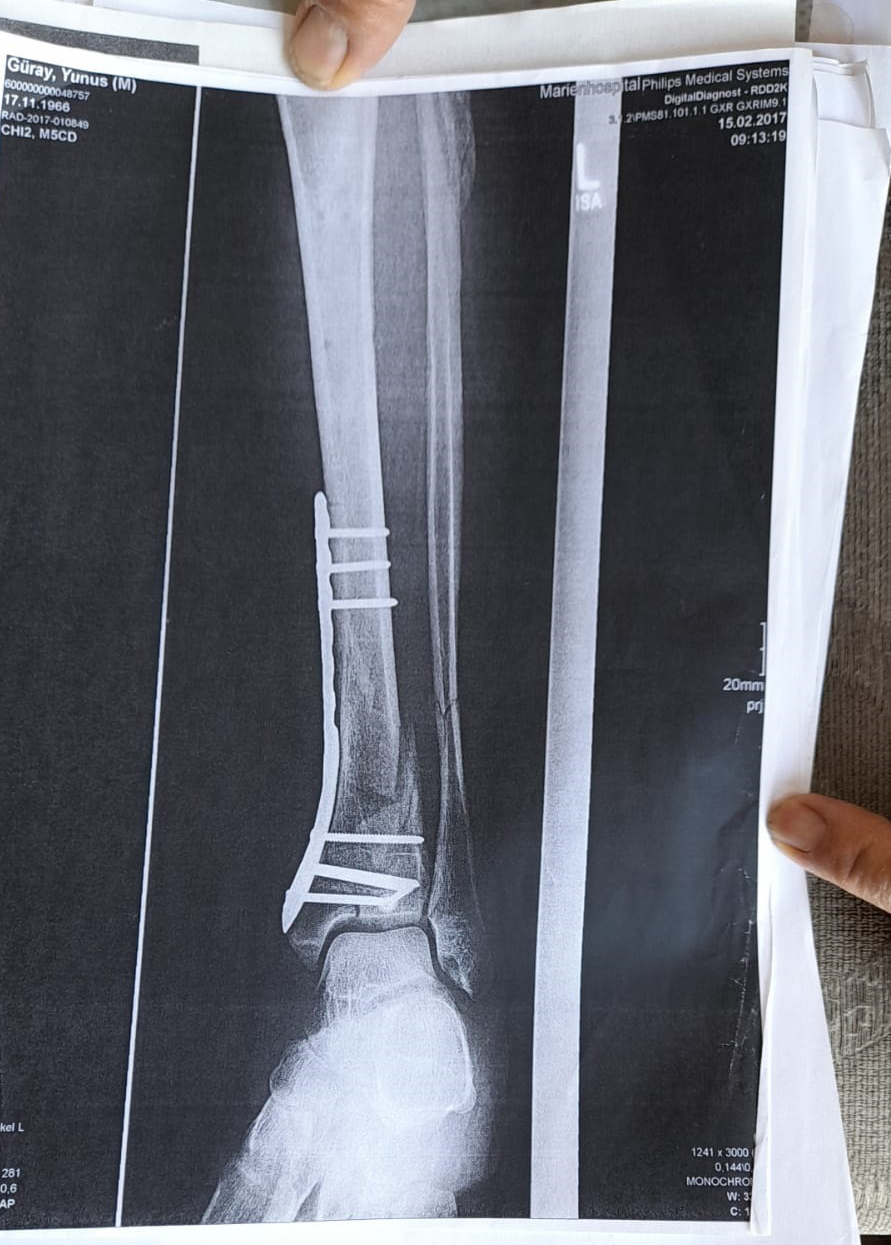

Olay yeriyle ilgili fotoğraf ve görüntüleri mahkemeye sunduklarını kaydeden Güray, "Ömrümü yediler, demir var ayağımda, sakat bıraktılar. Ayağı keseceklerdi neredeyse. Şu an kalıcı sakatlık var. 1 sene kendime gelemedim, 2 haftada bir ameliyata giriyordum. Almanya'da 3 ay hastanede kaldım ve ayağımda yüzde 3'lük engel oluştu" diye konuştu.

Tazminat miktarını düşük bulan Yunus Güray, şunları söyledi: "Benim uçak masrafım sadece 22 bin avro tuttu. 9 yıl oldu, bir tane çukur değildi. Adamlar kazmış, kazmış, bırakmış. Tam merkezde bu olay, hani ormanda bir yerde olur, 'Tamam benim de hatam var. Gittim de düştüm' derim. Ama şehrin merkezinde, etrafı çevrili değildi. Yemyeşil alan, gece vaktiydi. Ben mahkemeye verdim, o çukurları 3 ay sonra kapattılar. 6- 7 yerde kazılmış çukurlar vardı. Bir tane değildi. Ayağımda hala demir var. Adil bir karar olmadı."